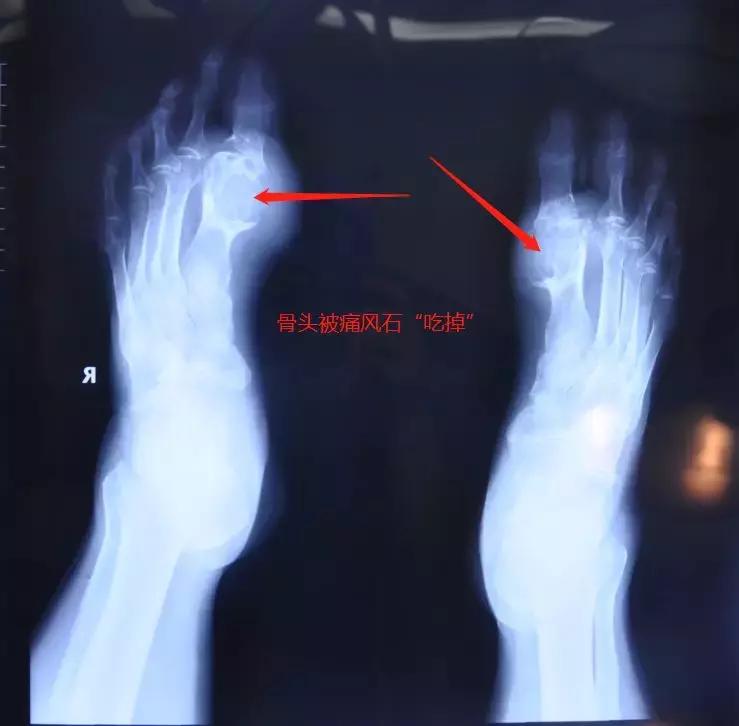

骨头已被“吃” 想保脚难上加难

现任北京麦瑞骨科医院康复中心的王捷主任,看到老同学的情况后也顿时感觉比较棘手,因为通过检查发现他左脚跖骨远端膨大,约大小4cm*3cm,第二趾骨近节膨大,跖屈背活动障碍;右脚趾骨远大肿胀,约大小4cm*4cm,脚踝膨大。患处及周围的骨头,都已经被痛风石‘吃’掉了,部分压迫到了神经和血管,如果不及时处理,会造成压迫处对应肢体障碍,还有可能造成肢体坏死,想保住脚更是难上加难。